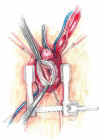

The main goal of minimally invasive surgery is to reduce the perioperative trauma, accelerate patient mobilization and reduce the length of hospital stay. Due to the development of modern technology, these treatments can be offered to a wider group of patients. For many years, aortic root surgery consisted of mechanical conduit implantation and, therefore, necessitated life-long anticoagulation. At present, in patients with aortic root aneurysm and significant aortic valve regurgitation, it is possible to perform minimal-access valve sparing surgical procedures. The current paper is a brief description of the surgical technique for aortic root aneurysm surgery with preservation of the patient's own valve using the David procedure.

Keywords: David procedure; V-shape ministernotomy; VSSR; minimally invasive surgery.